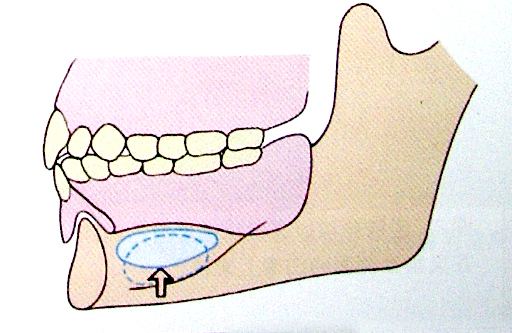

6.磨牙后垫(retromolar pad)

位于下颌最后磨牙牙槽嵴远端的粘膜软垫,覆盖在磨牙后三角上,由疏松的结缔组织构成,含黏液腺。

磨牙后垫的形态和位置比较稳定,作为排人工牙时的解剖标志;垂直向:下颌第一磨牙的颌平面与磨牙后垫的1/2处等高;

前后向:下颌第二磨牙应位于磨牙后垫前缘;

颊舌向:磨牙后垫颊面、舌面向前与下颌尖牙的近中面形成一个三角形。